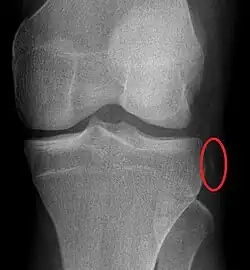

Plain lateral X-ray of the left knee showing a posterior knee dislocation[1] | |

Plain X-rays, CT scan, ultrasonography, or MRI may help with the diagnosis.[2][11] Findings on X-ray that may be useful among those who have already reduced include a variable joint space, subluxation of the joint, or a Segond fracture.[5]